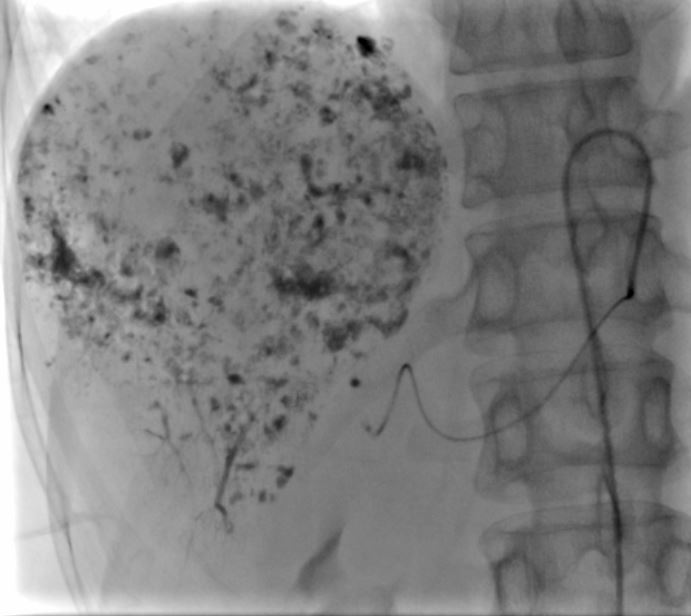

近日,潞河医院介入疼痛科为一名巨大肝血管瘤女性患者成功实施了介入栓塞治疗。患者梁女士今年49岁,体检时发现肝右叶血管瘤,最大径约9.6cm,且位于肝脏边缘,虽然破裂的几率较小,但一旦自发或外伤性破裂可能会给患者带来致命后果。梁女士入院后,介入疼痛科主任韩洋带领团队认真评估了术前影像学检查,并完善各项检验,排除治疗禁忌后,讨论制定了治疗方案。在与梁女士及家属充分沟通后,介入团队为其成功实施了微创介入栓塞治疗。术中腹腔干及肝动脉造影可见肝右叶巨大肿瘤染色,随着栓塞治疗的持续,可见该血管瘤内药物逐渐沉积,治疗完毕后再次造影显示原肿瘤供血动脉已封堵。手术成功完成,达到了治疗目的。术后,梁女士没有出现任何不良反应,现已顺利出院。

打药初期